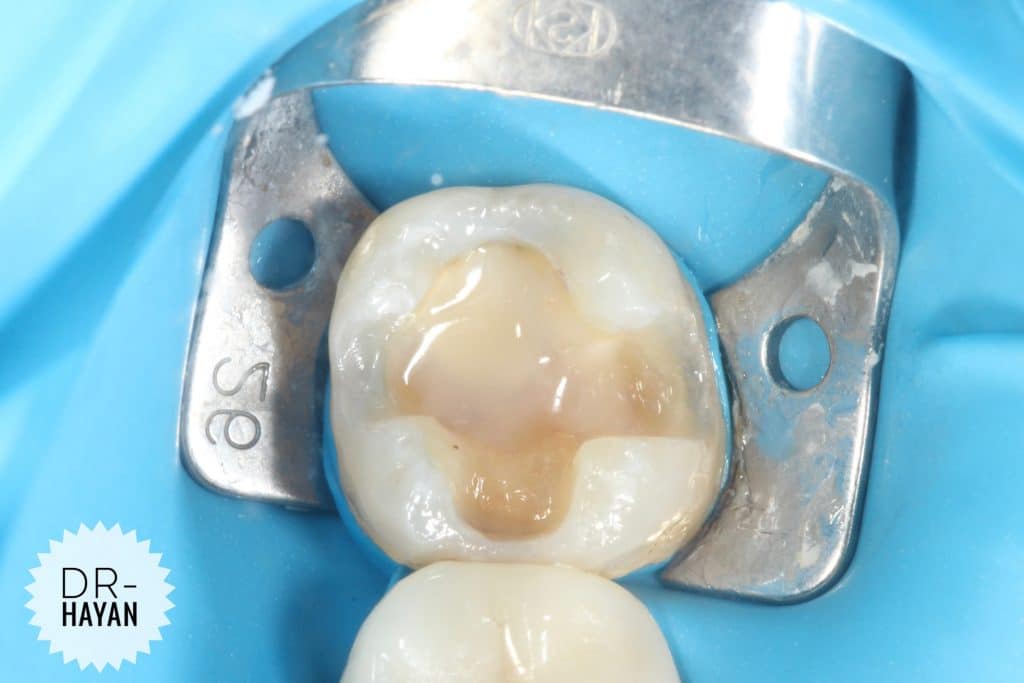

Finishing the floor And

Remove any sharp angle

IDPC

Selective etch

- finishing the gingival seat by sharp excavator

- After etching dis infected the cavity by CHX

And dry it only